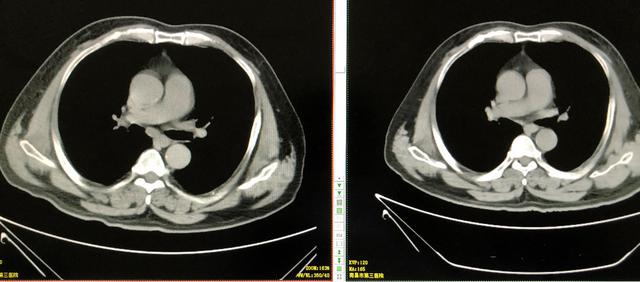

放疗结束后复查胸部CT提示肺部原发灶及纵膈转移淋巴结明显消退,放疗效果明显。

放疗后隆突下淋巴结明显消退

放疗后左下肺肿块完全消退